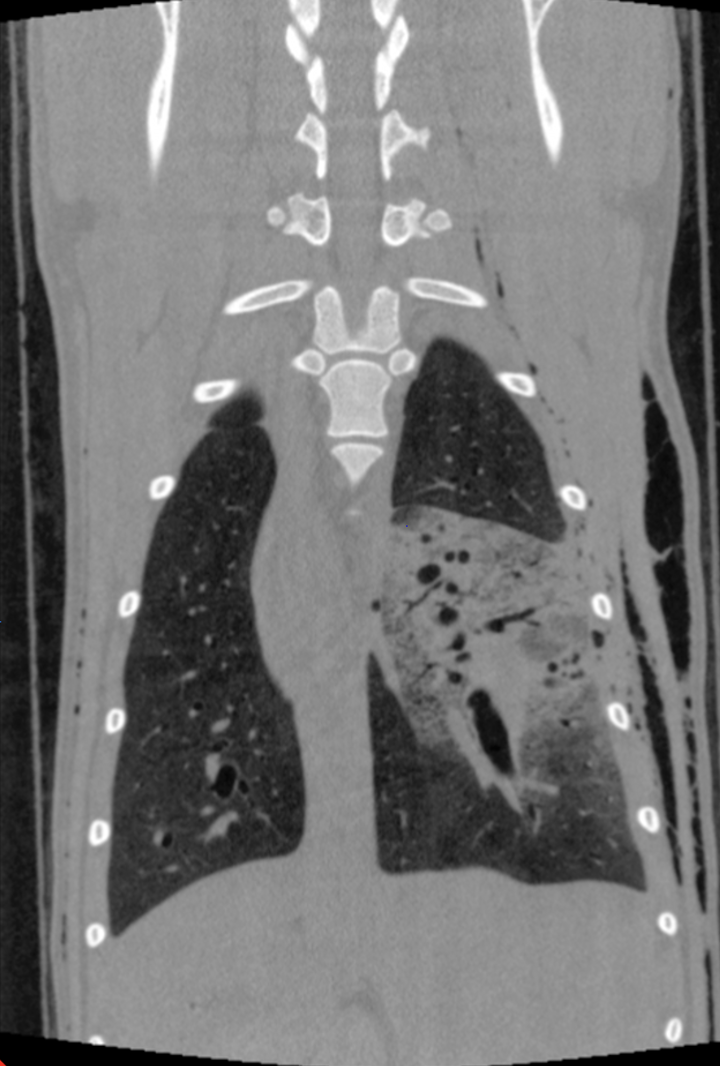

Thorax: Im Thorax wird das CBCT ebenso routinemäßig eingesetzt. Es erlaubt die Beurteilung von Raumforderungen, größeren parenchymatösen Veränderungen und mediastinalen Prozessen bei vergleichsweise kurzer Untersuchungszeit (Abb. 3 & 4).